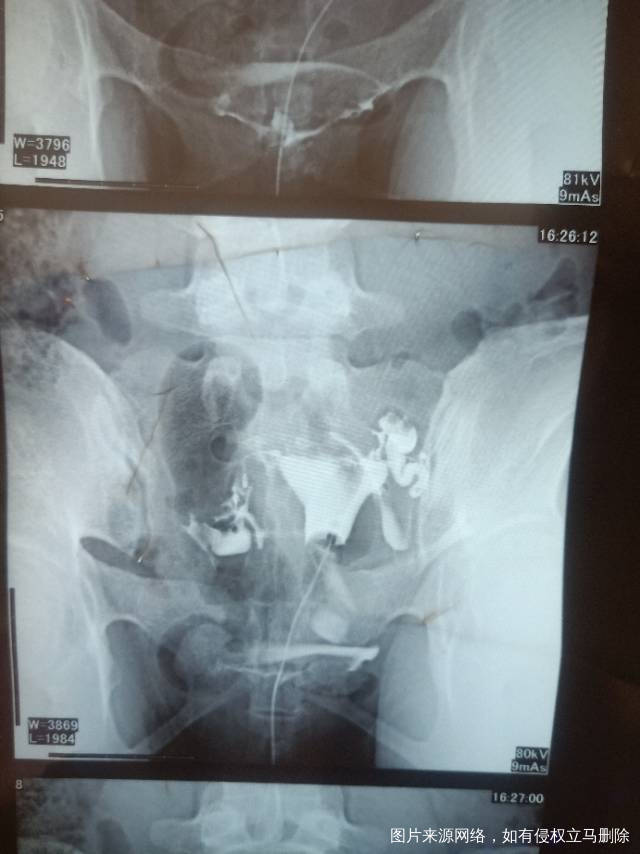

请问医生我这个造影有没有输卵管积水呀影不影响